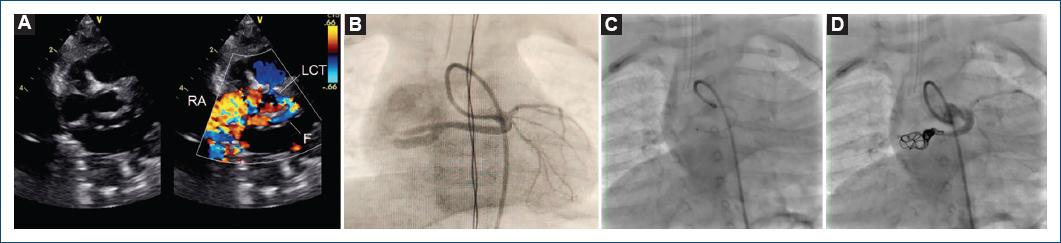

El primer caso es el de una niña de 4 meses, con peso de 5.8 kg, evaluada por presencia de soplo cardiaco continuo de grado III/VI en el borde esternal inferior izquierdo. Referencia de episodios de irritabilidad y llanto de etiología no precisada. Ecocardiograma transtorácico con dilatación del tronco coronario izquierdo y diámetro de 5.4 mm (Z-score + 10.1 SD) e imagen de fístula de la arteria coronaria izquierda drenando a la aurícula derecha (Fig. 1 A). La angiografía corroboró la dilatación del tronco coronario izquierdo con emergencia, a nivel del tercio distal, de un vaso de 3.8 mm de diámetro y 10.9 mm de longitud que se dirigía a la aurícula derecha bifurcándose en dos: uno de 3 mm y otro de 2.2 mm de diámetro (Fig. 1 B). Se posiciono un catéter Judkind derecho de 4 Fr en el ostium de la coronaria y se avanzó una guía de 0.14 × 180 CHOICE PT floppy (Boston Scientific/Scimed, Inc., Maple Grove, Minnesota, USA) hasta la porción terminal de la fístula, y sobre esta se posicionó un microcatéter Excelsior SL 10 (Stryker Neurovascular, Freemont, California, USA) de 1.7 Fr en el tercio distal de la fístula (Fig. 1 C), y se colocaron cuatro coils Target 360 electrolargables de 5 × 10 mm (uno), 4 × 8 mm (dos) y 3 × 8 mm (uno), logrando la oclusión completa del flujo en el tercio distal (Fig. 1 D). La paciente evolucionó satisfactoriamente y egresó a las 24 horas del procedimiento.

Figura 1 A: vista en el eje corto de grandes vasos en bidimensional y Doppler color mostrando dilatación de la arteria coronaria izquierda. B: angiografía previa en la que se aprecia el trayecto de la fístula. C: microcatéter en la porción distal de la fístula. D: angiografía de control mostrando la oclusión total de la fistula. F: fístula; LCT: tronco coronario izquierdo; RA: auricula derecha.